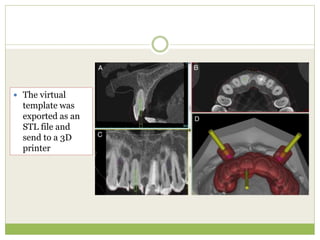

 The virtual

template was

exported as an

STL file and

send to a 3D

printer